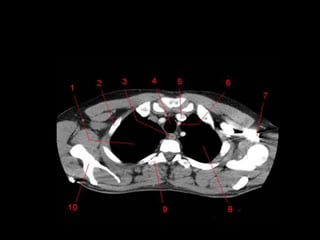

TC mediastino superior